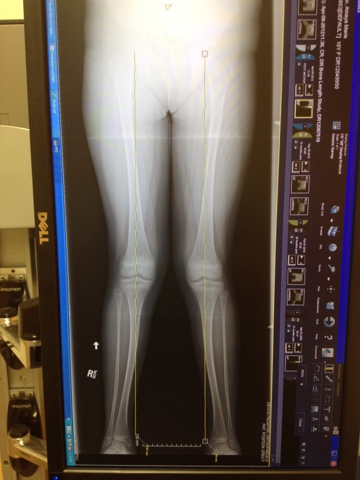

We are at Dr. Forness' office today, this is our 6 week check up, they are repeating X-rays today, and will be comparing the lengthwise X-rays from 2009.

He was comparing 2009 to 2012 to see if the axis (angle and direction from the hip down to the ankle) has gotten any worse. The X-ray came back and he says that it is about the same. When Amaya was 8, the initial problems were figured out. At that time, they said she had "knock knees". This has always been apparent, so not a surprise to us. The measurement between her ankles at that time was 7 cm, and is now 11 cm.

Dr. Forness has recommended for her to have surgery. Both of her femurs, and both of her tibias are actually growing crooked, or rounded, when they should be straight.

| 4/2012 |

| 4/2012 closer view |